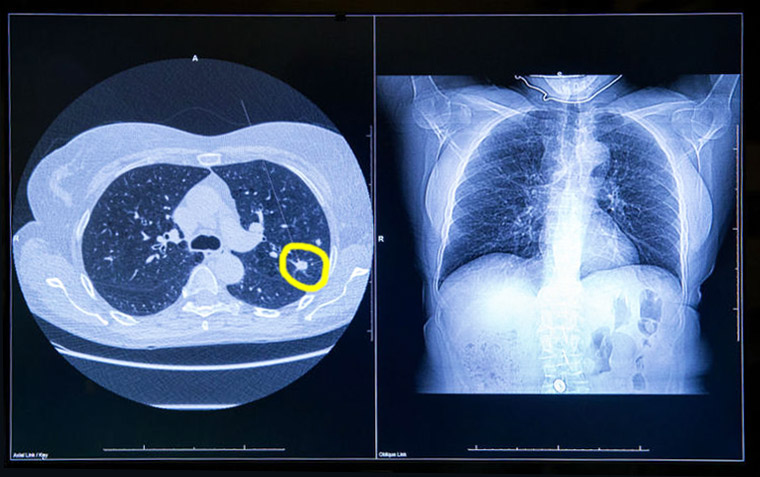

Del total de participantes, el 12,4% recibió un diagnóstico de cáncer de pulmón en el plazo de un año. Se realizaron procedimientos invasivos al 16,2% de todos los participantes y al 7,3% de aquellos sin cáncer de pulmón eventual. Alrededor del 60% de los participantes recibió atención acorde con las directrices, y aproximadamente un tercio recibió cuidados menos intensivos. Las tasas de procedimientos invasivos en aquellos sin cáncer fueron bajas. Annals of Internal Medicine, diciembre de 2025.

Detección del cáncer de pulmón mediante TAC de baja dosis en Francia: resultados finales del estudio DEP KP80

17 octubre 2024

Este estudio demostró la viabilidad y eficacia del cribado del cáncer de pulmón en un contexto de la vida real, en el que la mayoría de los cánceres de pulmón se diagnostican en una etapa temprana y se extirpan quirúrgicamente. Nuestros resultados también destacaron la importancia de la participación en cada ronda, subrayando el hecho de que optimizar la organización es un objetivo principal. eBioMedicine, noviembre de 2024.

Resultados del rastreo de cáncer de pulmón con tomografía computada en E.E.U.U.

04 abril 2022

Se ha registrado un cambio desde la introducción del rastreo de cáncer de pulmón hacia mayor número de diagnósticos de cáncer de células no pequeñas en estadio I, lo que coincide con un aumento en la  supervivencia. Sin embargo, los pacientes que no eran blancos y los que vivían en áreas de mayor privación tenían una menor tasa de detección en estadio I, lo que destaca la necesidad de esfuerzos para aumentar el acceso a las pruebas de detección en los EE. UU. British Medical Journal, 30 de marzo de 2022.

Eficacia del rastreo de cáncer de pulmón en poblaciones seleccionadas

13 septiembre 2021

Los resultados del estudio británico UKLS muestran reducción de la mortalidad por cáncer de pulmón a partir del rastreo en pacientes de alto riesgo con una única tomografía computada de baja dosis. Un metaanálisis de nueve ensayos aleatorios proporciona un apoyo inequívoco para la detección del cáncer de pulmón en grupos de riesgo identificados. The Lancet Regional Health Europe, 11 de septiembre de 2021.